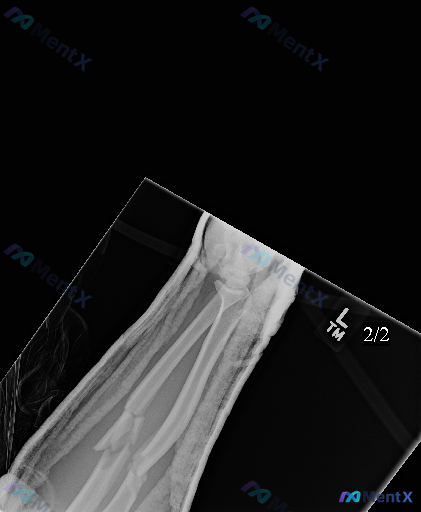

- 投照与体位:左前臂斜位,可见大面积高密度石膏/夹板外固定影,存在一定伪影

- 骨骼情况:左侧尺骨、桡骨骨干中段均见粉碎性骨折,皮质多处中断,断端有明显移位及成角畸形,可见尖锐骨折片

- 关节与软组织:腕关节未见明显脱位;骨折周围软组织密度增高、轮廓增宽,考虑创伤性水肿(与外固定材料重叠)

- 其他骨结构:非骨折区骨小梁尚清晰,未见明确骨质疏松或溶骨性病变;骨皮质、髓腔符合成年人特征